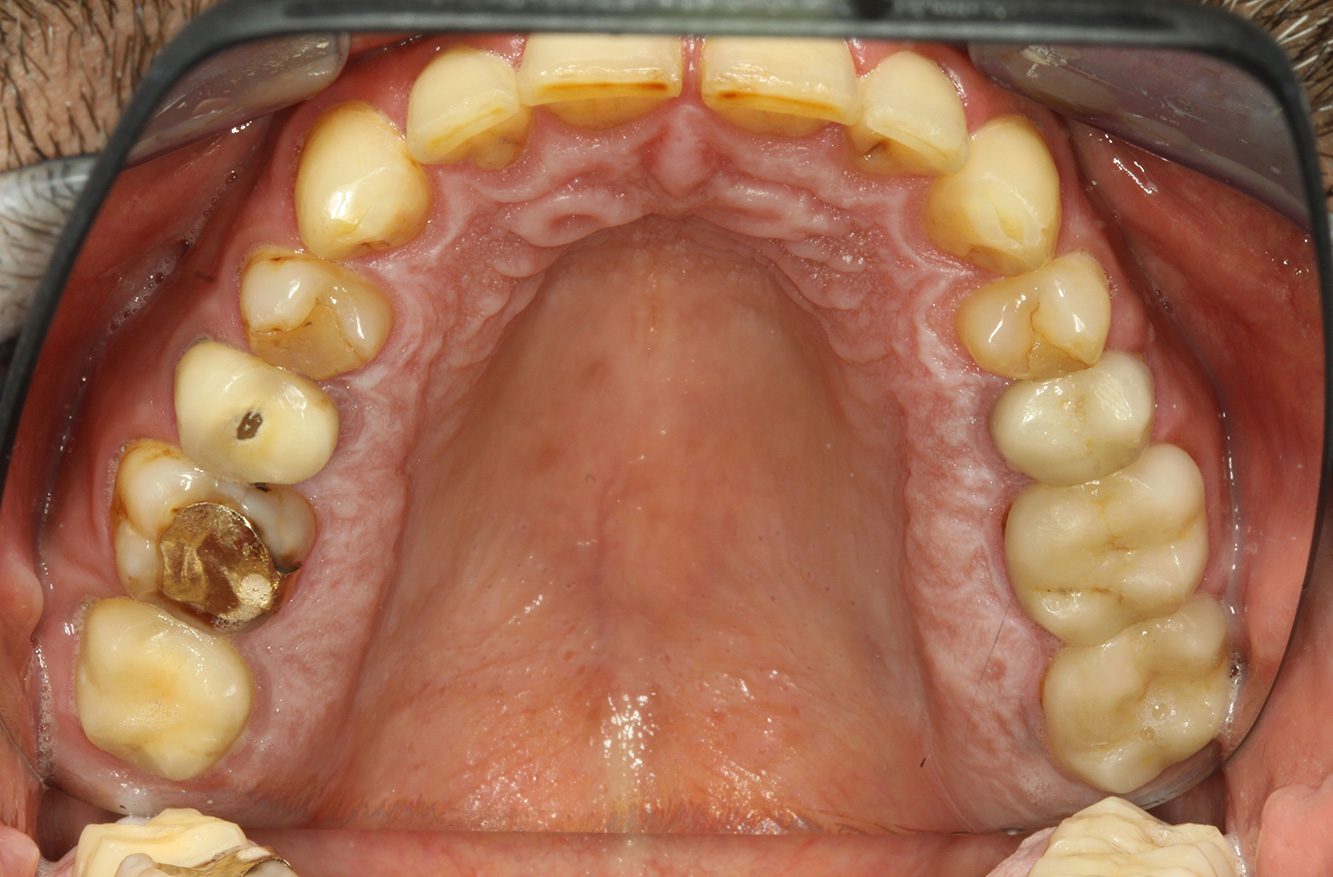

The endocarditis patient with active caries lesions*

The patient is 39 years old and has previously undergone aortic valve replacement due to valve failure and endocarditis. ASS 100 is taken regularly as an anticoagulant. In terms of lifestyle, the patient’s diet is classified as caries-promoting due to the regular consumption of sugary foods and the fact that six to seven meals are consumed daily. The patient’s oral health indicates a moderate risk of caries, with active lesions. The risk of periodontitis is low, but gingivitis is present. The following recommendations are made for prophylactic treatment.

No specific instrument recommendations can be determined for the prophylaxis session. Targeted application of air and rotary polishing can be used to gently reduce plaque and stains on the restoration edges, and to reduce recolonization niches for cariogenic bacteria (19).

Fluoridation is recommended to further support the prevention of caries, and especially to prevent new formation around the restoration edges, and to seal the root surfaces. Both of these measures can reduce the teeth’s sensitivity to temperature.

Due to the active caries lesions and the associated risk of progression, a shortened recall interval of three to four months is recommended.